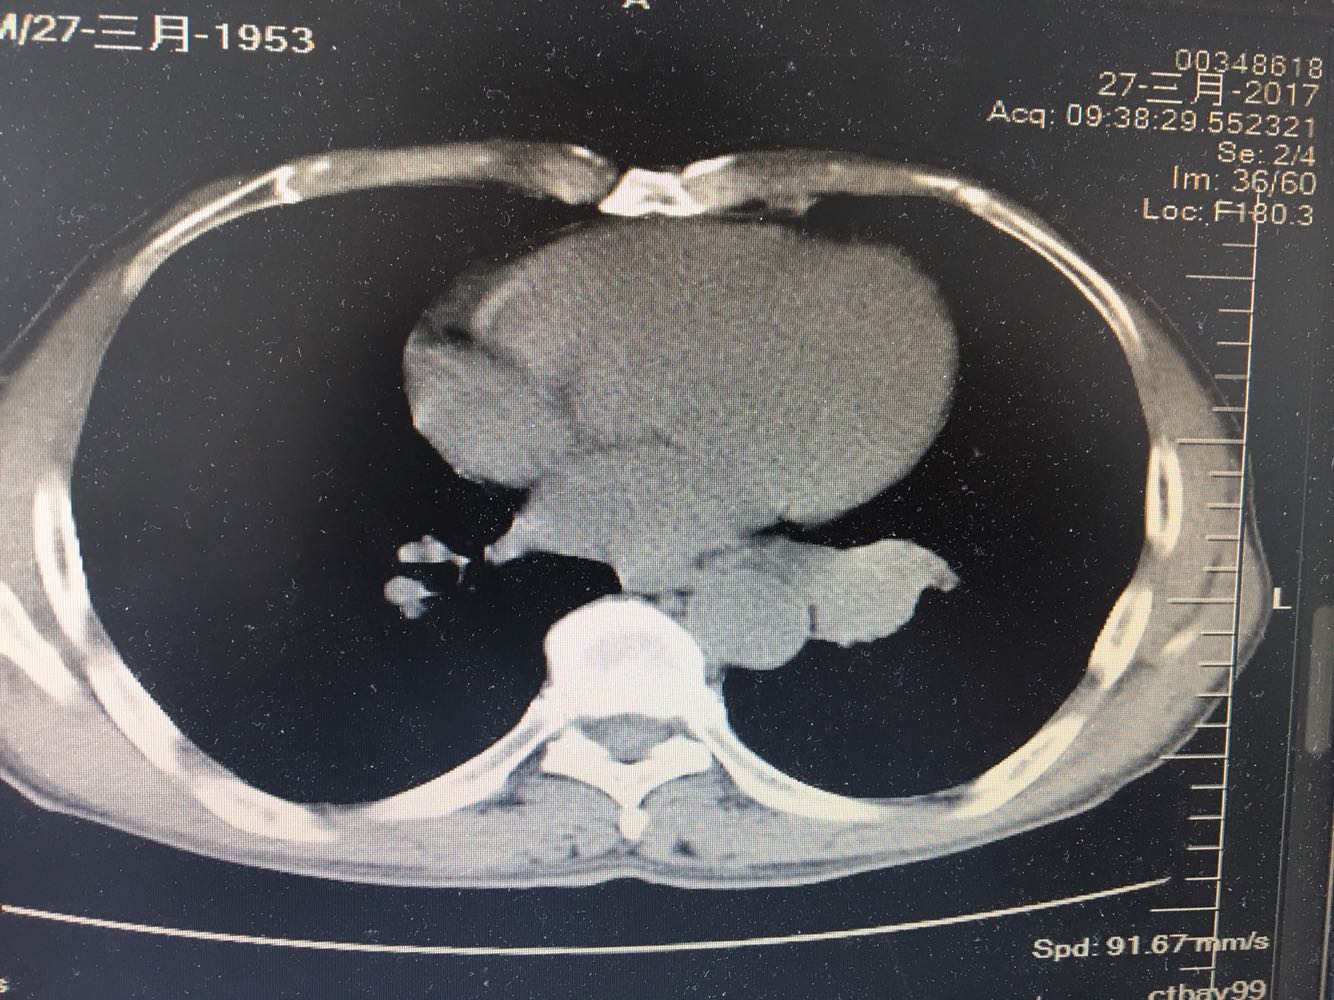

左肺下叶鳞癌

男,63岁,咳嗽1个月入院,患者自述1个月前无诱因咳嗽,阵发性干咳,无痰,时有血丝,无发热,左胸痛,活动后气短,静滴头孢13天无好转,门诊查肺CT后以 肺占位收入我科,病来饮食睡眠可,体重明显下降。既往疝气术后1年,吸烟史30年,每日1包。

左肺癌

左肺中央型肺癌,是否可以手术,还是化疗,放疗,靶向治疗?